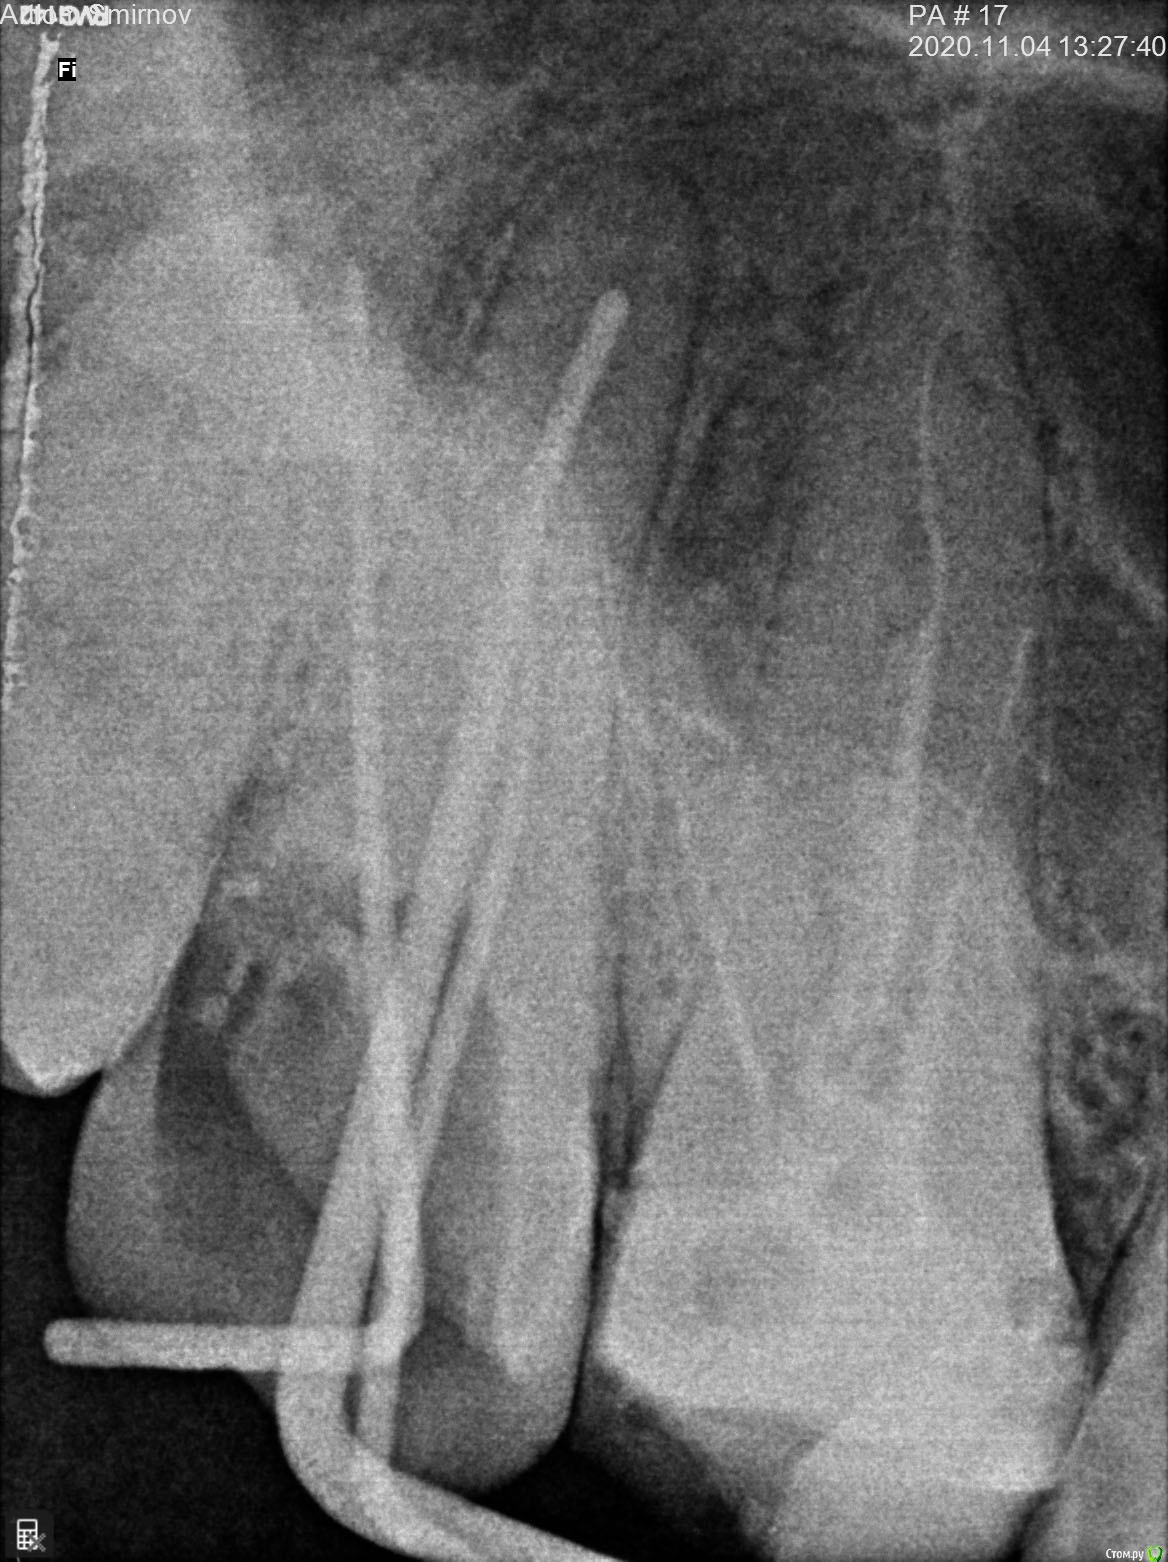

Artiom_Kl Опубликовано 26 ноября, 2020 Поделиться Опубликовано 26 ноября, 2020 Доброго времени суток! Буду очень Вам признателен, если дадите совет. Ситуация такова: Стоматолог запломбировал 3 канала и поставил временную пломбу (на месяц, до следующего приема, когда он должен уже поставить постоянную пломбу). Однако уже 3 недели, как я испытываю практически постоянный дискомфорт в зубе, который на 2 неделе уже перерос в ноющую боль, хоть и незначительную и не постоянную (сейчас уже 3 неделя-ситуация без изменений). Обратился к стоматологу. Он посмотрел визуально ротовую полость и сказал, что всё нормально, боль какое-то время может быть. И, по его словам, после установки постоянной пломбы боль через некоторое время должна исчезнуть. Нерв, как он добавил, беспокоить не может, так как он его умертвил. Однако меня терзают сомнения, что каналы запломбированы качественно. Я запросил у него снимки, сделанные после пломбирования каналов. Взгляните, пожалуйста, на рентгеновские снимки. Можно ли по ним судить о качестве пломбирования каналов ? Ссылка на комментарий

АнтонТЛТ Опубликовано 26 ноября, 2020 Поделиться Опубликовано 26 ноября, 2020 Сделайте кт, возможно у зуба есть ещё один корневой канал с остатками нерва. 1 Ссылка на комментарий